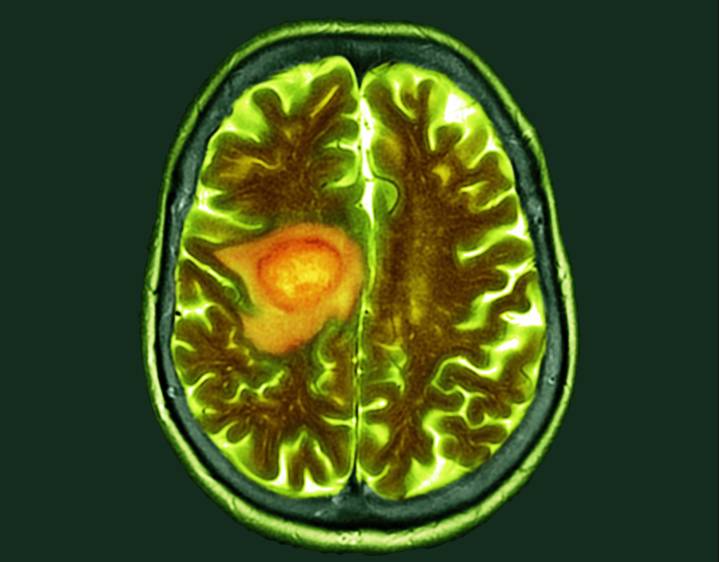

Glioblastoma remains one of the most lethal solid tumors, with median survival measured in months despite surgery, radiation, and chemotherapy. Immunotherapies that transformed treatment for other cancers have repeatedly fallen short in glioblastoma, largely because the tumor microenvironment suppresses nearly every arm of the immune response. Against this backdrop, researchers have been searching for platforms that can both kill tumor cells and disrupt the immunosuppressive ecosystem that protects glioblastoma from attack.

A new preclinical study from Mass General Brigham, published in Nature Cancer , demonstrates that a rationally engineered herpes simplex virus (HSV-1) may provide exactly that combination. The team designed a next-generation oncolytic virus capable not only of tar